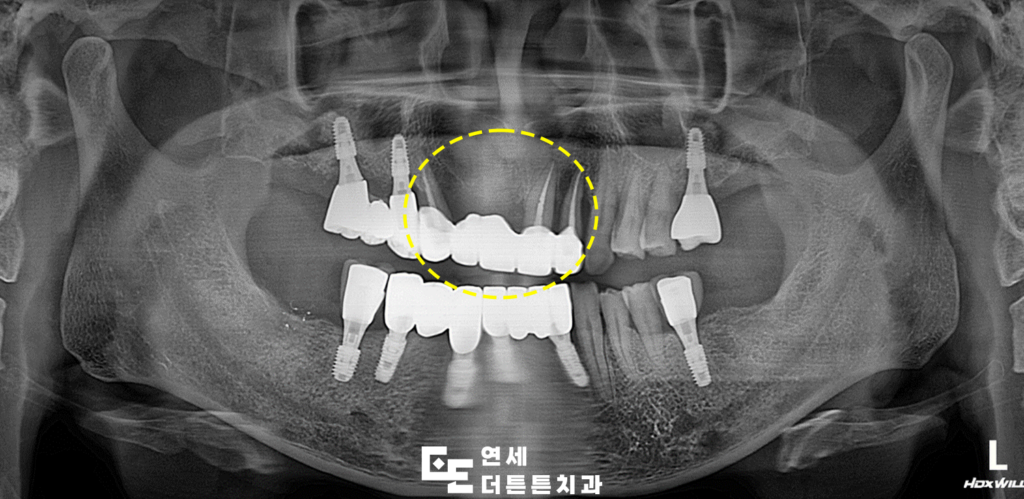

겉으로 보기에는 문제가 없는 듯 보였으나

파노라마를 촬영해 보니, 지탱하고 있던 양쪽

지대치 뿌리 쪽 염증으로 인해 잇몸뼈가 거의

남아 있지 않을 만큼 녹아 있었고

살려 쓰기에는 무리가 있다고 판단되어

발치 후 임플란트 식립 계획을 수립하였습니다.

먼저 기존의 브릿지를 제거하고

자연치들을 발치하였습니다.